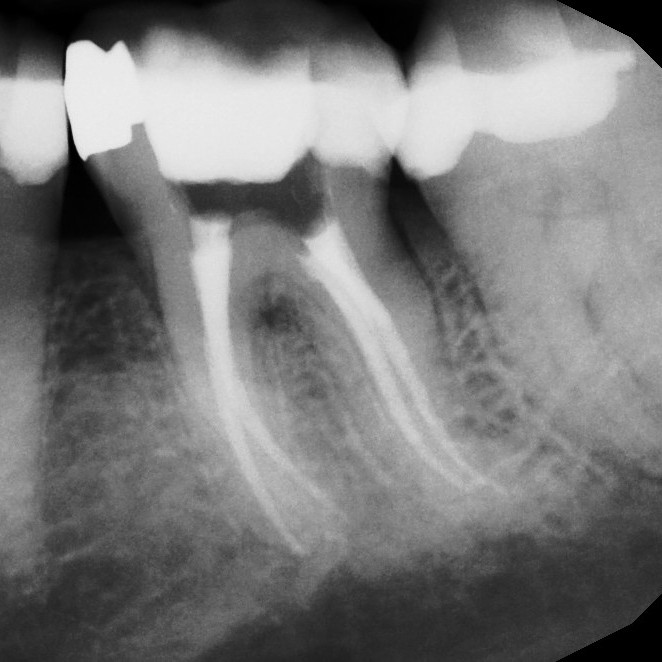

Sometimes, a tooth that has already undergone root canal therapy may not heal as expected or may develop new problems months or even years later. In these cases, endodontic retreatment offers a second chance to save the tooth. During this procedure, the existing filling materials are carefully removed from the canals, the inside of the tooth is cleaned again, and any hidden or untreated areas are addressed before the canals are sealed once more. This process allows your dentist to correct any issues and give the tooth the best possible chance for long-term success.

Thanks to modern tools and techniques, retreatment is a precise and effective procedure that can often be completed comfortably under local anesthesia. Many patients are surprised to learn that retreatment is no more uncomfortable than the original root canal. By choosing retreatment instead of extraction, you preserve your natural tooth, maintain your smile's appearance, and avoid the more complex and costly process of replacing a missing tooth.